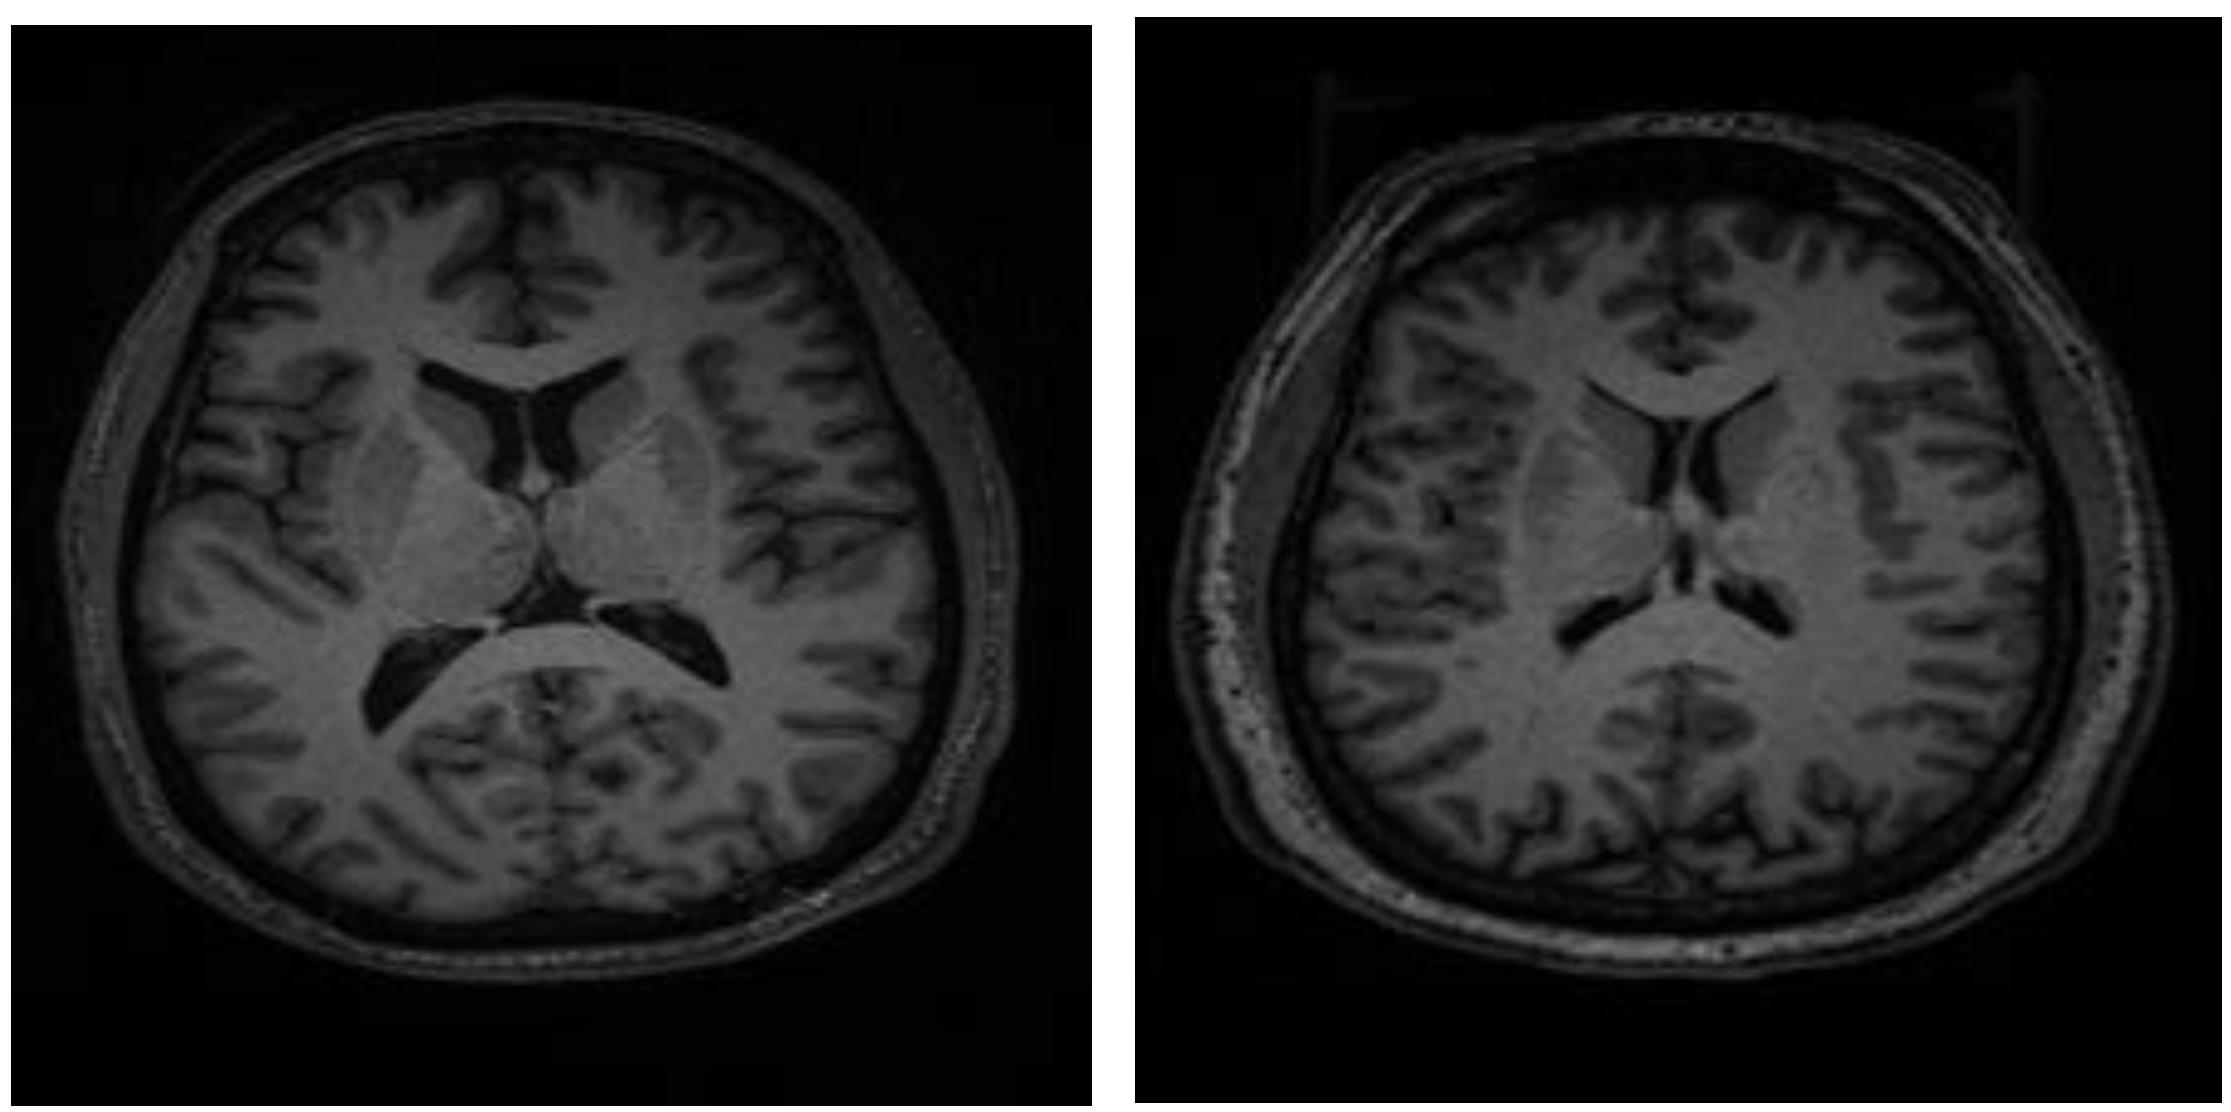

To integrate the T1-weighted MR images into the ResNet50 architecture, they were uniformly resized to 224 × 224 pixels. Figure 1 illustrates representative MR images acquired from SCH and BD patients. While the T1-weighted MR volumes encompassed 216 axial slices per participant, our analysis focused on the central 32 slices to optimize computational efficiency and maintain image quality. Subsequent to slice selection, all images underwent normalization to standardize intensity values. To mitigate overfitting, data augmentation techniques were employed, carefully considering the reliability of medical images. Specifically, rotation and brightness adjustments were incorporated into the augmentation pipeline, ensuring that the generated images remained consistent with the characteristics of real MR scans. Finally, all images were scaled to a range of 0 to 1 for numerical compatibility within the neural network.

Figure 1. 224 × 224 resized MR images of patients with bipolar disorder (left) and schizophrenia (right).